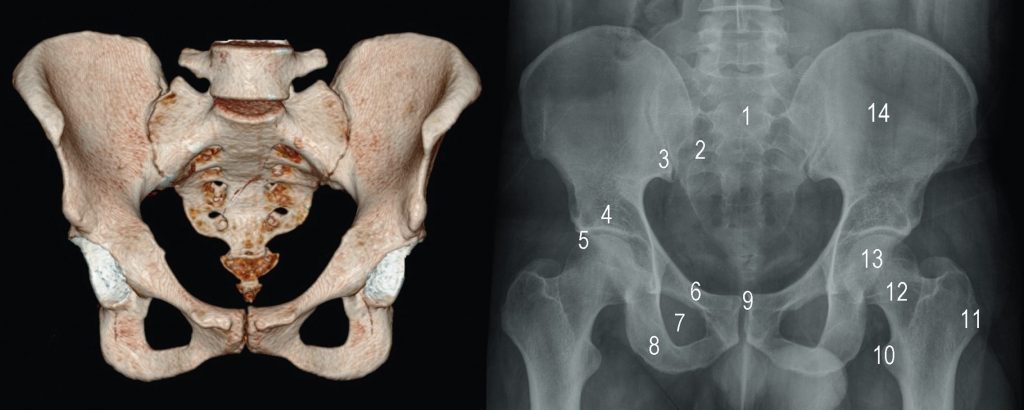

Fig. 74.7 Bassin : radiographie de face.

1. Sacrum. 2. Foramen sacré. 3. Articulation sacro-iliaque. 4. Acétabulum. 5. Articulation coxofémorale. 6. Branche supérieure du pubis. 7. Foramen obturateur. 8. Branche inférieure du pubis. 9. Symphyse pubienne. 10. Petit trochanter. 11. Grand trochanter. 12. Col fémoral. 13. Tête fémorale. 14. Aile iliaque.

Source : CERF, CNEBMN, 2022.